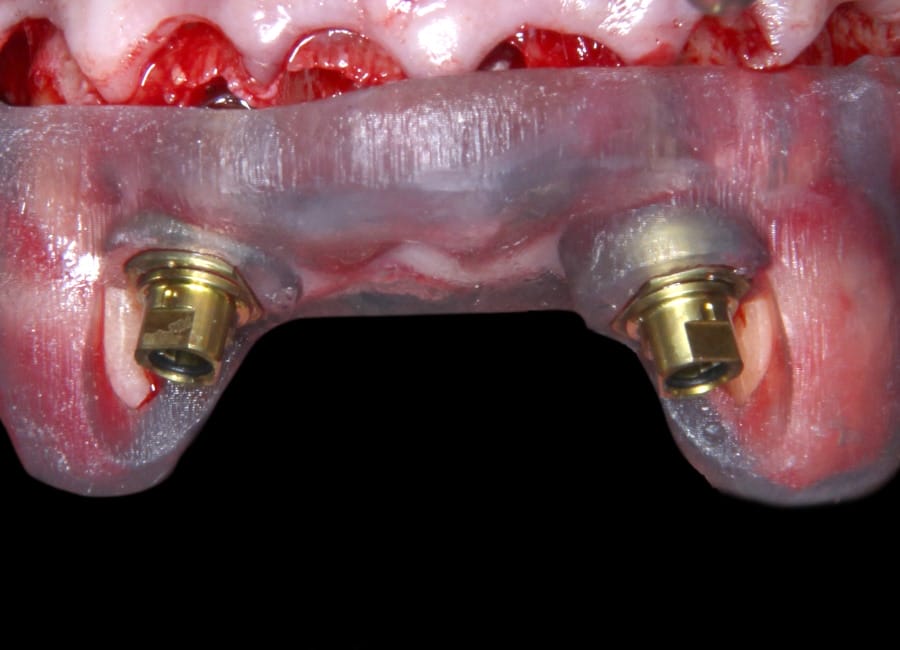

Surgical phase